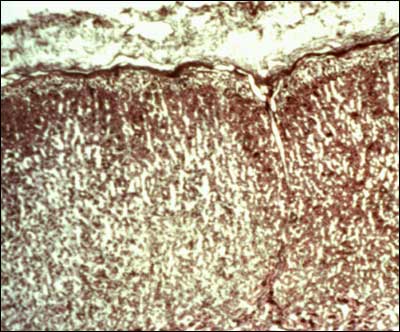

Published May 16, 2013 at 400 × 332 in ACTH Action on the Adrenals.

Figure 3. Extensively vascularized adrenal cortex